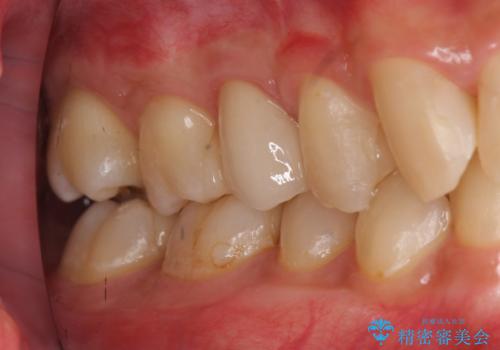

放置した虫歯 歯ぐきの中まで虫歯でも、しっかり健康的な部分を引っ張り出して、きちんと処置します。

歯の健康な部分を矯正治療で引っ張り出してから、虫歯治療を行なっています。

終了時